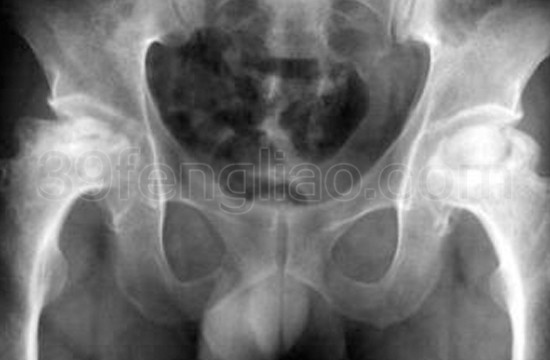

五、×线表现。骨纹理细小或中断、股骨头囊肿、硬化、扁平或塌陷。